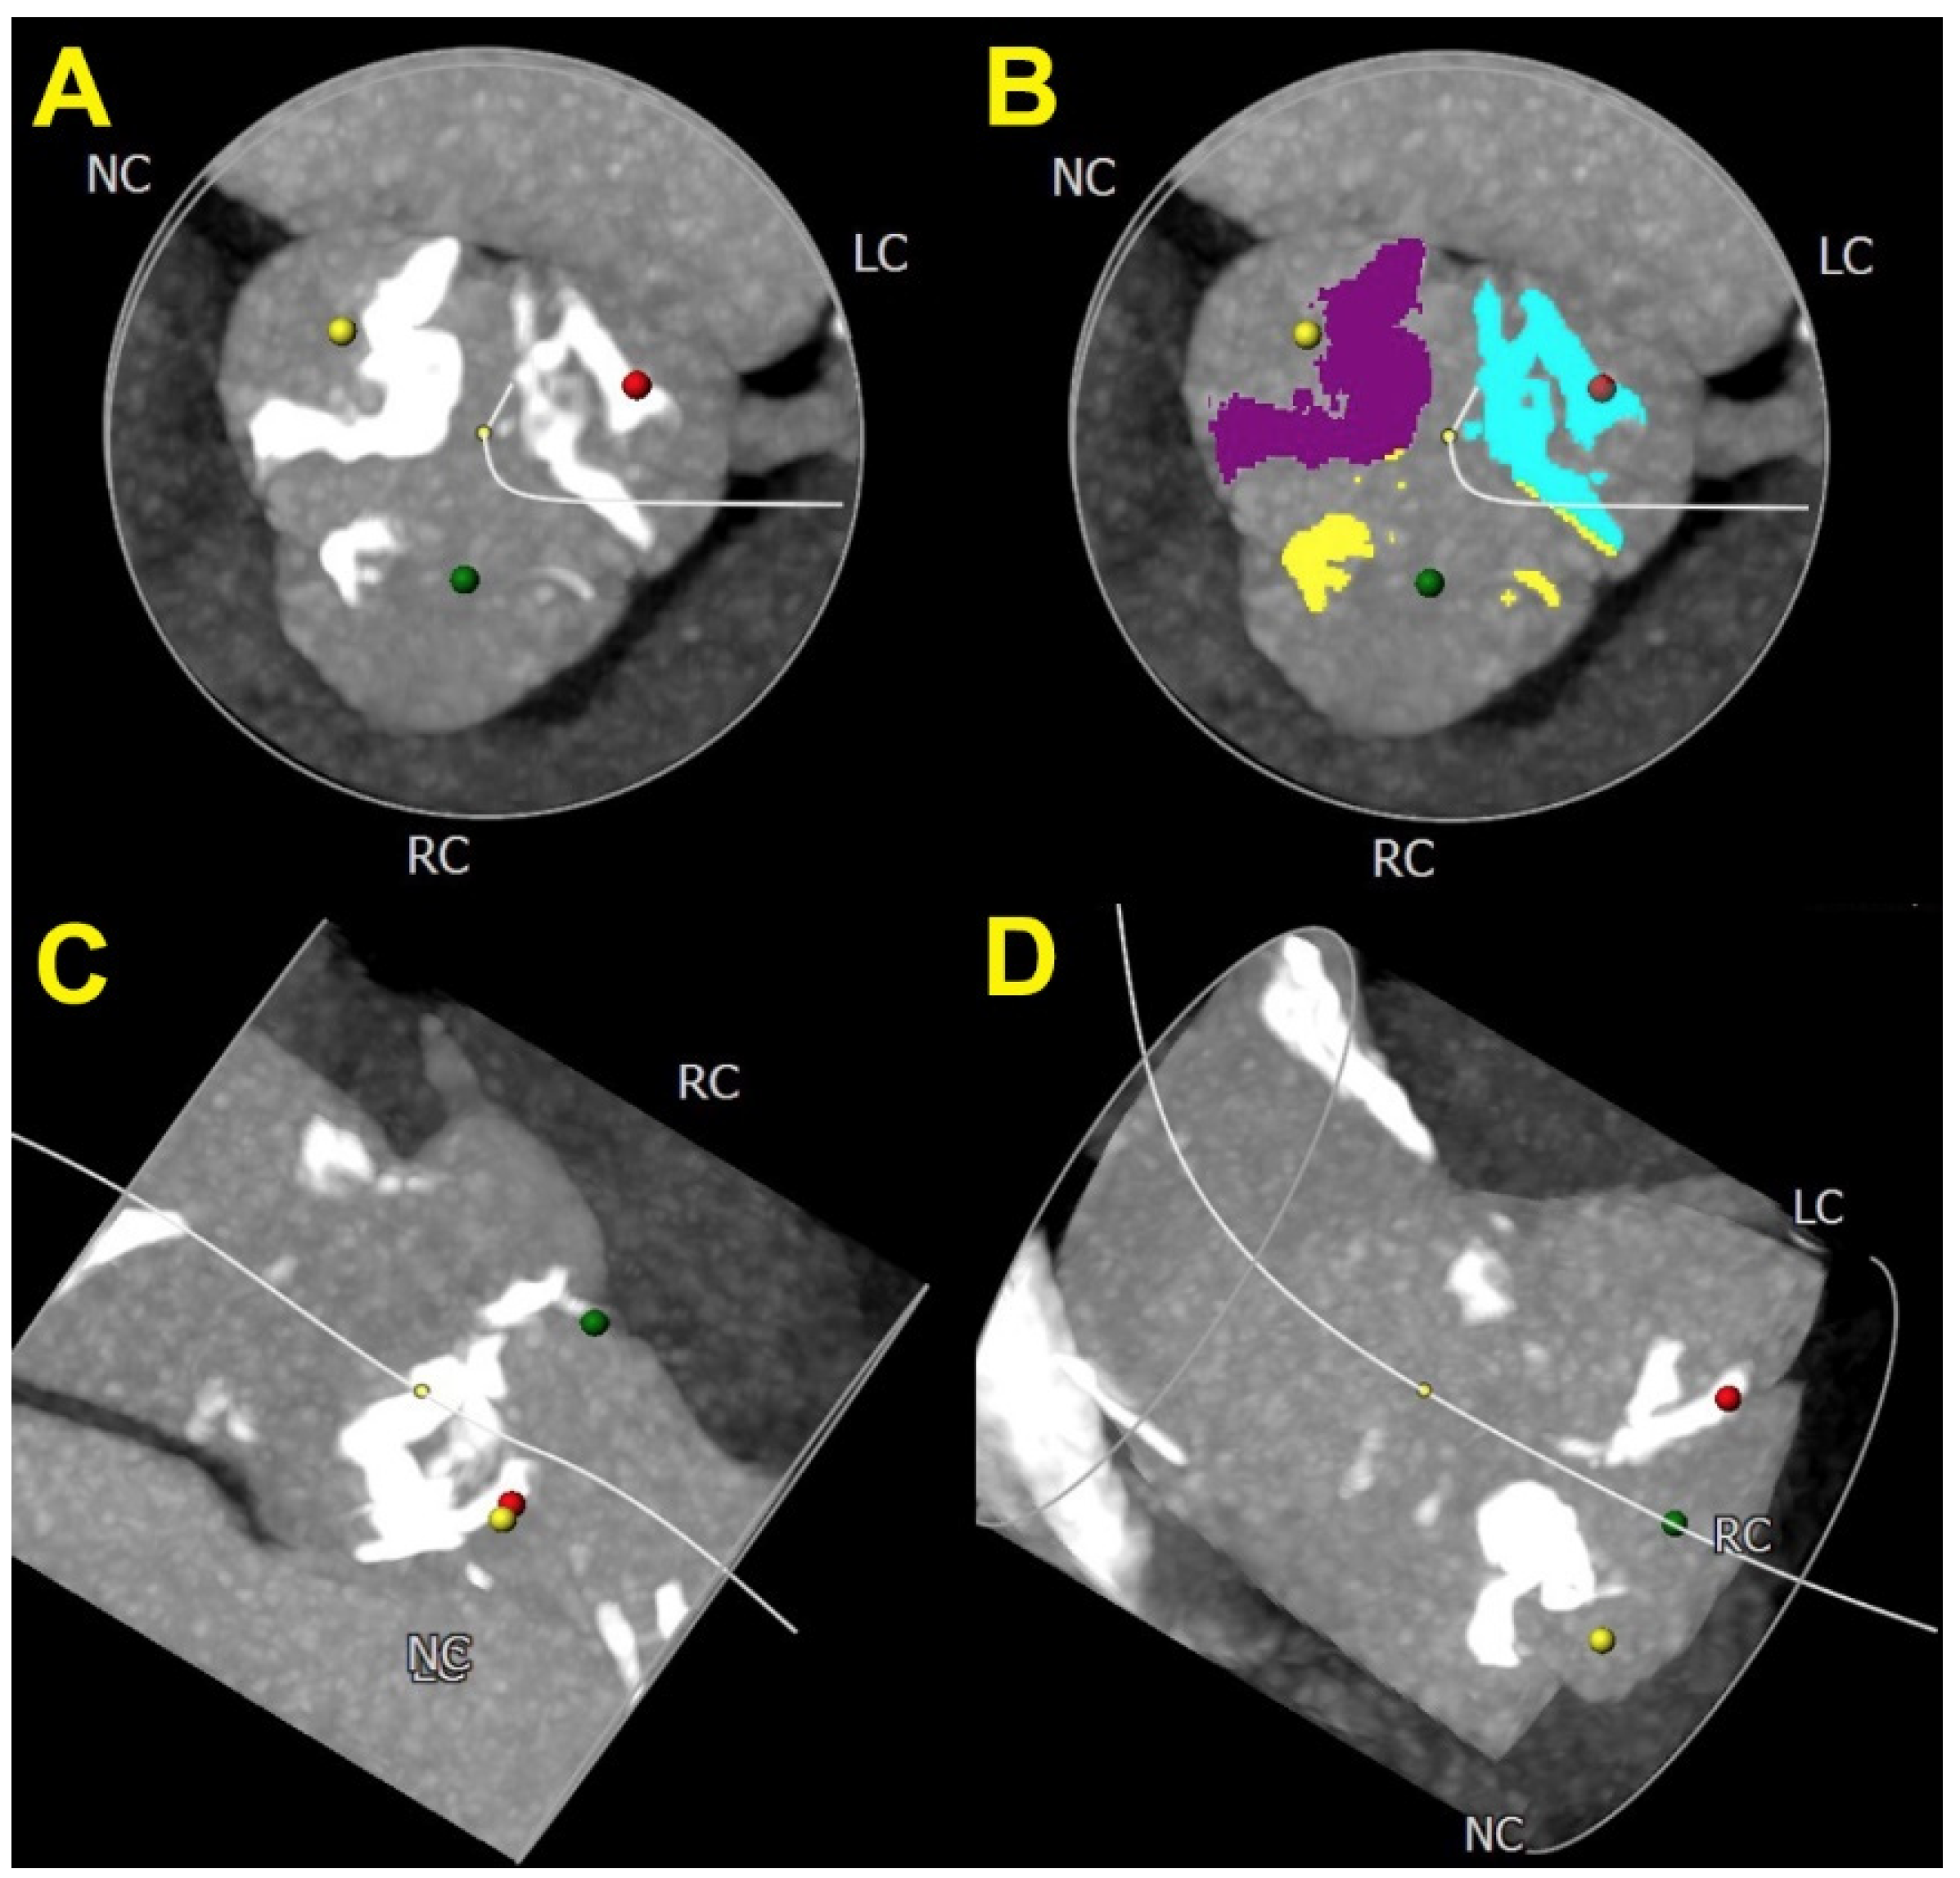

7. Computed Tomography